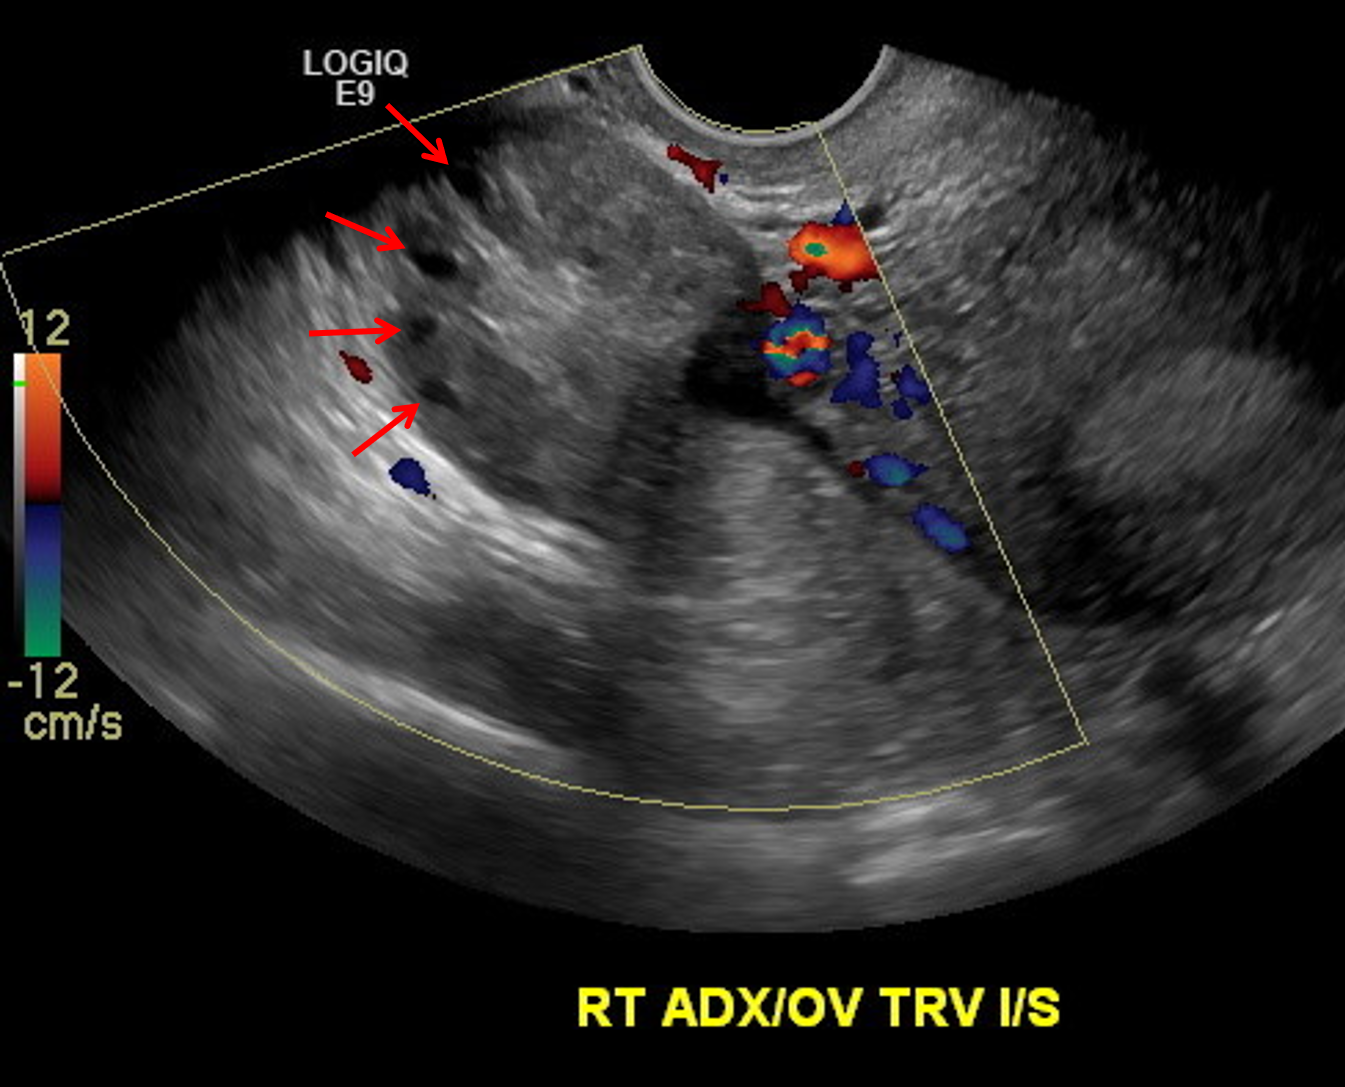

Sample ReportMarkedly enlarged right ovary with heterogeneous echotexture, peripheralization of ovarian follicles, and minimal internal vascularity, concerning for ovarian torsion.

Echogenic mass along the medial aspect of the right ovary with internal “dot dash” appearance is consistent with a dermoid cyst and is the likely lead point for ovarian torsion.